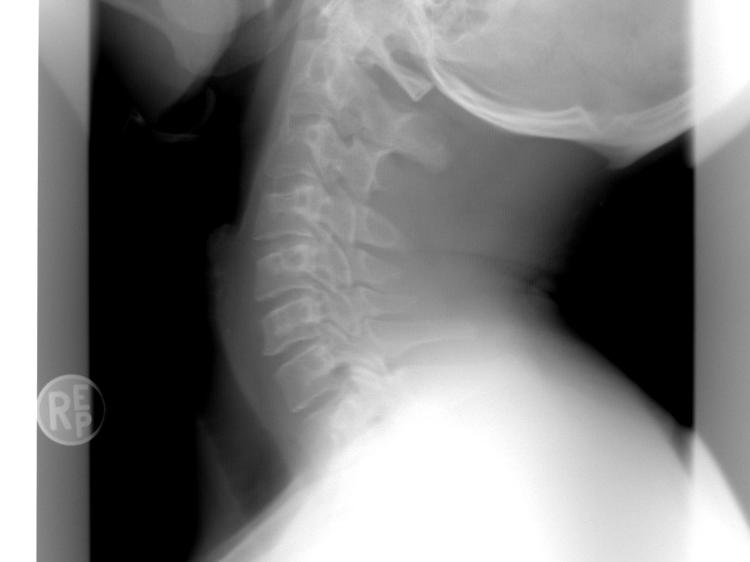

面对颈椎响和突出感,既不用过度焦虑,也不能完全忽视,以下4步科学应对,能有效保护颈椎: 第一步:先区分弹响类型——生理性弹响的特点是偶尔出现、声音清脆、无伴随不适;病理性弹响则是频繁出现、声音沉闷或粗糙、伴有颈部酸痛、僵硬。如果是病理性弹响,建议及时到正规医疗机构就诊。 第二步:做针对性检查——如果不确定突出的原因,或出现病理性弹响,最好到骨科或康复科就诊,做颈椎X线检查(查看颈椎的生理曲度、棘突位置是否正常)、CT(观察颈椎小关节的结构是否错位)或磁共振(明确椎间盘是否突出、神经是否受压),通过检查明确是生理结构还是病理改变,避免盲目处理。 第三步:针对性调理——如果确诊为颈椎关节紊乱,医生通常会建议进行康复理疗,比如颈椎牵引(通过牵引增加颈椎间隙,缓解关节压力)、手法复位(由专业康复师操作,纠正小关节错位,注意不可自行尝试)、物理因子治疗(如中频电疗、超声波治疗,缓解肌肉紧张和疼痛)。同时可以在医生指导下进行颈椎康复锻炼,比如“米字操”(动作要缓慢、轻柔,每个方向停留3-5秒,避免过度用力)、颈部后伸训练(靠墙站立,头部缓慢向后仰,感受颈部肌肉拉伸,停留5秒后放松,重复10次),通过锻炼增强颈部肌肉力量,维持颈椎稳定性。需要注意的是,特殊人群(如孕妇、有严重颈椎病、骨质疏松的患者)在进行康复锻炼或理疗时,必须在医生指导下进行。 第四步:日常防护要到位——颈椎的保护关键在日常,以下几点要做好:保持正确坐姿,电脑屏幕与眼睛平齐,肩膀放松,腰背挺直,避免长时间低头(看手机时把手机举到与眼睛平齐的高度);选择合适的枕头,高度以8-12厘米为宜,能支撑颈椎的生理曲度,避免过高或过低导致颈椎变形;每坐30-40分钟起身活动,做几个缓慢的颈部后伸、左右侧屈动作,缓解颈椎压力;注意颈部保暖,避免空调或风扇直接吹颈部,寒冷刺激会导致肌肉痉挛,加重颈椎不适。